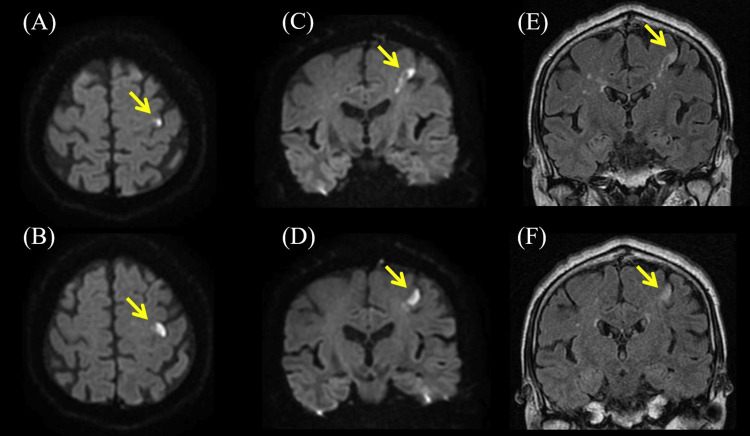

Figure 1. The results of brain magnetic resonance imaging (MRI).

(A, B) Diffusion-weighted brain axial MRI showing hyperintensity in precentral knob (PK) on left precentral gyrus (arrowheads). (C, D) Diffusion-weighted brain coronal MRI showing hyperintensity on left precentral gyrus (arrowheads). (E, F) T2-weighted fluid-attenuated inversion recovery brain coronal MRI showing hyperintensity on the left precentral gyrus corresponded with diffusion-weighted imaging (arrowheads).

| First dorsal interosseous muscle | 3 | Ulnar nerve | C8, T1 |

Blood tests were unremarkable except for slightly elevated C-reactive protein (0.32 mg/dL), blood glucose (118 mg/dL), and γ-glutamyl transpeptidase (75 U/L). Nerve conduction studies revealed normal results. Diffusion-weighted and T2-weighted fluid-attenuated inversion recovery brain MRI showed hyperintensity in PK on the left precentral gyrus (Figure 1). Brain magnetic resonance angiography showed no occlusion of the major artery. Transesophageal echocardiography showed no thrombus, right-to-left shunt, or aortic arch lesion. Carotid artery echocardiography revealed plaques on both bulbuses and thickening of the intima media thickness (IMT), but no increment of blood flow velocity (Figure 2).